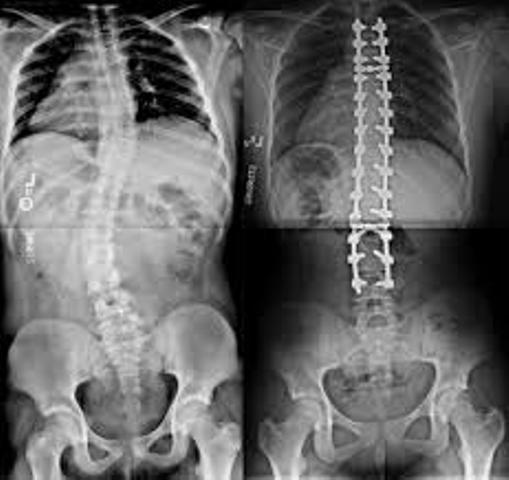

Neuro Department of the hospital have all the major facilities. The Corporate Hospital is having, starting from receiving Neuro Trauma in State of the Art Emergency Department, shifting to Medical or Surgical ICU depending upon diagnosis till shifting to Modular Neuro O.T. suite of Neurologist to take care of these types of patients. All kinds of brain tumour, brain trauma etc and other type of surgeries are performed in The Corporate Hospital. All operated Neuro Surgery cases are treated in Post OP. in Neuro ICU where dedicated Neuro Team is available.